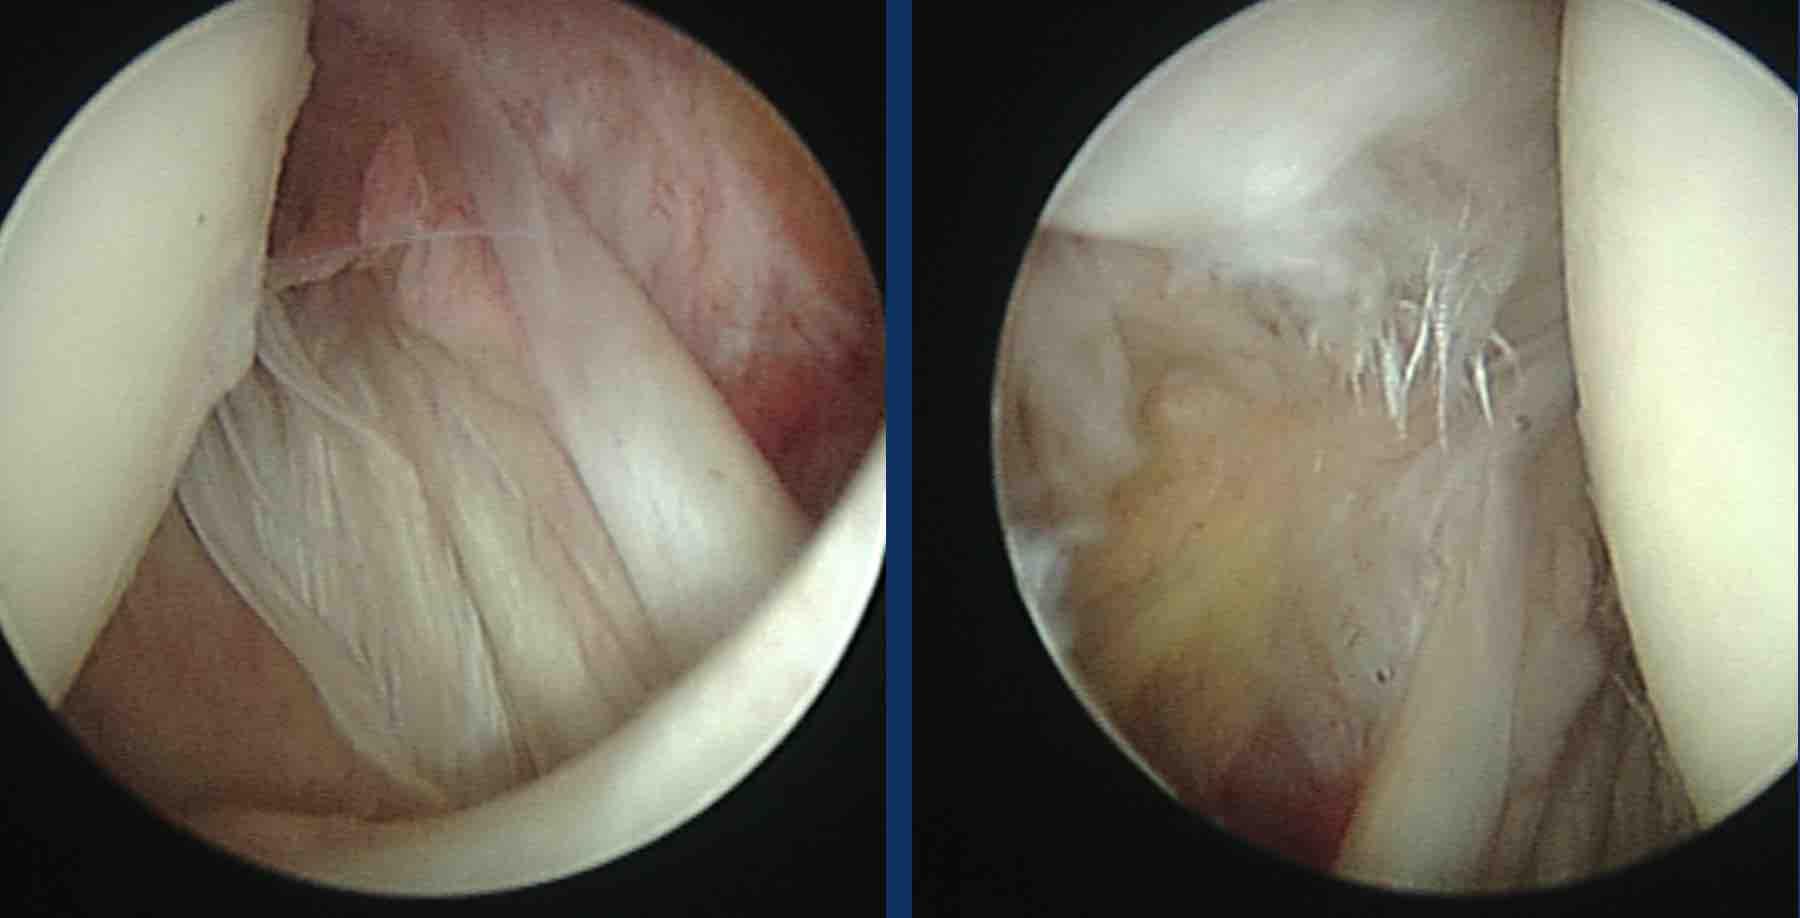

Gân dưới vai (Subscapularis)

Rách gân dưới vai thường gặp sau chấn thương trực tiếp, dạng cánh tay cưỡng bức kết hợp xoay ngoài, hoặc trong bối cảnh trật khớp vai ra trước tái phát.

Hình ảnh

Rách gân dưới vai sau chấn thương trực tiếp.

Có hình ảnh co rút gân dưới vai về phía trước kèm phù nề quanh gân trên các chuỗi xung PD-weighted mặt phẳng axial và chuỗi xung T2W xóa mỡ mặt phẳng coronal (dấu hoa thị).

Gân cơ nhị đầu không bị trật (đầu mũi tên).

Bệnh nhân này có tiền sử chấn thương trực tiếp vùng khớp vai phía trước.